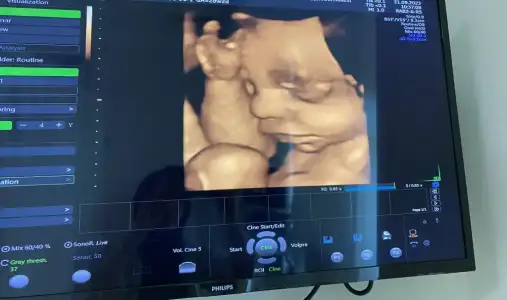

28+2den selamlar, yine benimki önden gidiyor biraz ama doktor geçen ay demek ki gelişim dönemindeymiş, şimdi haftasına yakın dedi. 1198 gr olmuş boyu da 35 cm😍

Eklentiler

• IMG_6913.webp